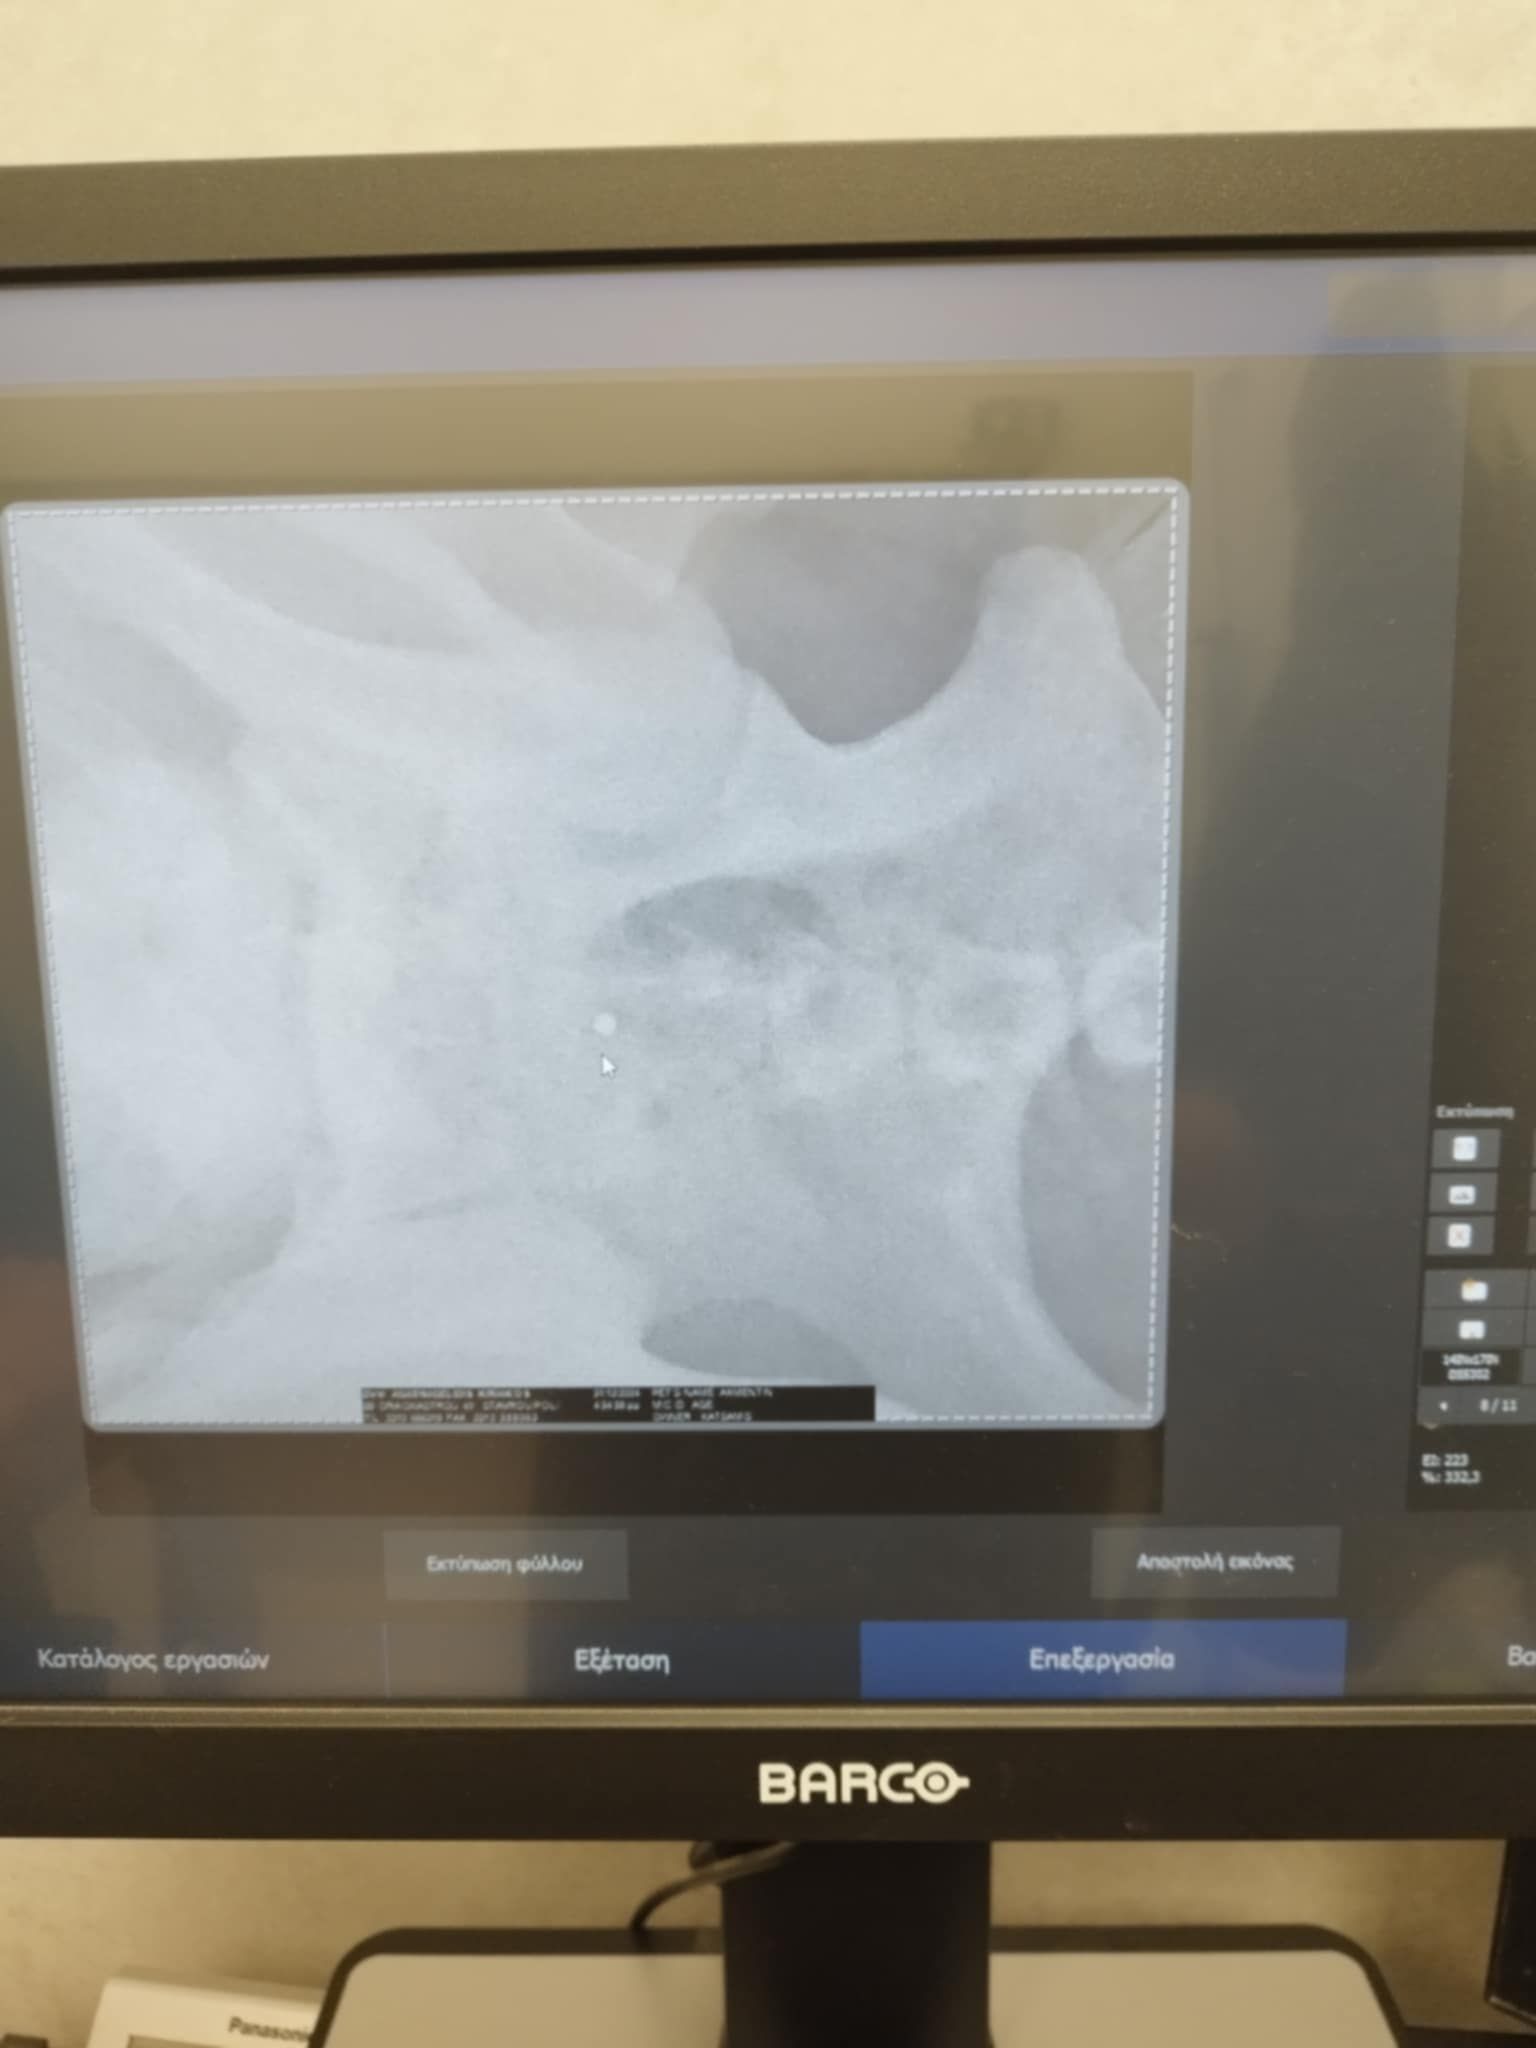

Τελικά οι ακτινογραφίες έδειξαν τι έχει συμβεί. Ο σκύλος είναι πυροβολημένο. Δεκάδες σκάγια εντοπίστηκαν στο σώμα του, στην σπονδυλική στήλη με αποτέλεσμα το ζώο να μην μπορεί όχι μόνο να κινηθεί αλλά και να αφοδεύσει με αποτέλεσμα στο έντερο να έχουν συσσωρευθεί κόπρανα.

Η Ευτυχία Πουρνάρα με αφορμή το περιστατικό επισήμανε τα εξής στις 3 Ιανουαρίου: «ΦΙΛΟΙ ΜΟΥ ΒΟΗΘΗΣΤΕ ΑΥΤΟ ΤΟ ΠΛΑΣΜΑ ΝΑ ΓΙΝΕΙ ΚΑΛΑ ΓΙΑΤΙ ΕΝΩ ΜΟΥ ΕΙΠΑΝ ΠΡΕΠΕΙ ΝΑ ΤΟ ΧΤΥΠΗΣΕ ΑΥΤΟΚΙΝΗΤΟ  ΣΥΓΚΛΟΝΙΣΤΙΚΑ ΟΤΑΝ ΟΙ ΑΚΤΙΝΟΓΡΑΦΙΕΣ ΔΕΙΞΑΝ ΟΤΙ ΤΟ ΚΟΡΜΑΚΙ ΤΟΥ ΣΚΥΛΑΚΟΥ ΕΙΤΑΝ ΓΕΜΑΤΟ ΣΚΑΓΙΑ ΔΙΑΣΠΟΡΑΣ ΕΝΑ ΤΟ ΒΡΕΙΚΕ ΣΤΗΝ ΣΠΟΝΔΥΛΙΚΗ ΣΤΥΛΗ Ο ΓΙΑΤΡΟΣ ΜΟΥ ΚΥΡΙΟΣ ΚΑΡΑΜΗΤΡΟΣ ΜΟΥ ΕΔΩΣΕ ΑΓΩΓΗ  ΤΟ ΖΩΟ ΔΕΝ ΜΠΟΡΟΥΣΕ ΝΑ ΑΦΟΔΕΥΣΗ ΚΑΙ ΠΡΙΣΤΗΚΕ ΚΑΝΟΥΜΕ ΑΓΩΝΑ ΝΑ ΤΟ ΒΟΗΘΗΣΟΥΜΕ ΤΟ ΚΑΛΟ ΕΙΝΑΙ ΟΤΙ ΑΙΣΘΑΝΕΤΑΙ ΤΑ ΠΟΔΑΡΑΚΙΑ ΤΟΥ ΘΑ ΣΑΣ ΠΩ ΝΕΟΤΕΡΑ ΤΟ ΚΑΘΑΡΜΑ ΠΟΥ ΤΟ ΠΥΡΟΒΟΛΗΣΕ  ΕΥΧΩΜΕ ΑΥΤΟ ΠΟΥ ΕΚΑΝΕ ΝΑ ΤΟ ΒΡΕΙ ΜΠΡΟΣΤΑ ΤΟΥ ΜΗΝ ΞΕΧΝΑΤΕ ΒΟΗΘΗΣΤΕ  ΕΧΩ ΑΓΩΝΑ ΜΠΡΟΣΤΑ ΜΟΥ ΓΙΑ ΝΑ ΣΩΘΕΙ ΣΤΕΙΛΤΕ ΜΗΝΝΥΜΑ ΣΤΟ ΜΕΣΣΕΝΤΖΕΡ  ΕΥΧΑΡΙΣΤΩ ΠΟΛΥ ΤΗΛ 6946348888 ΚΙΛΚΙΣ».